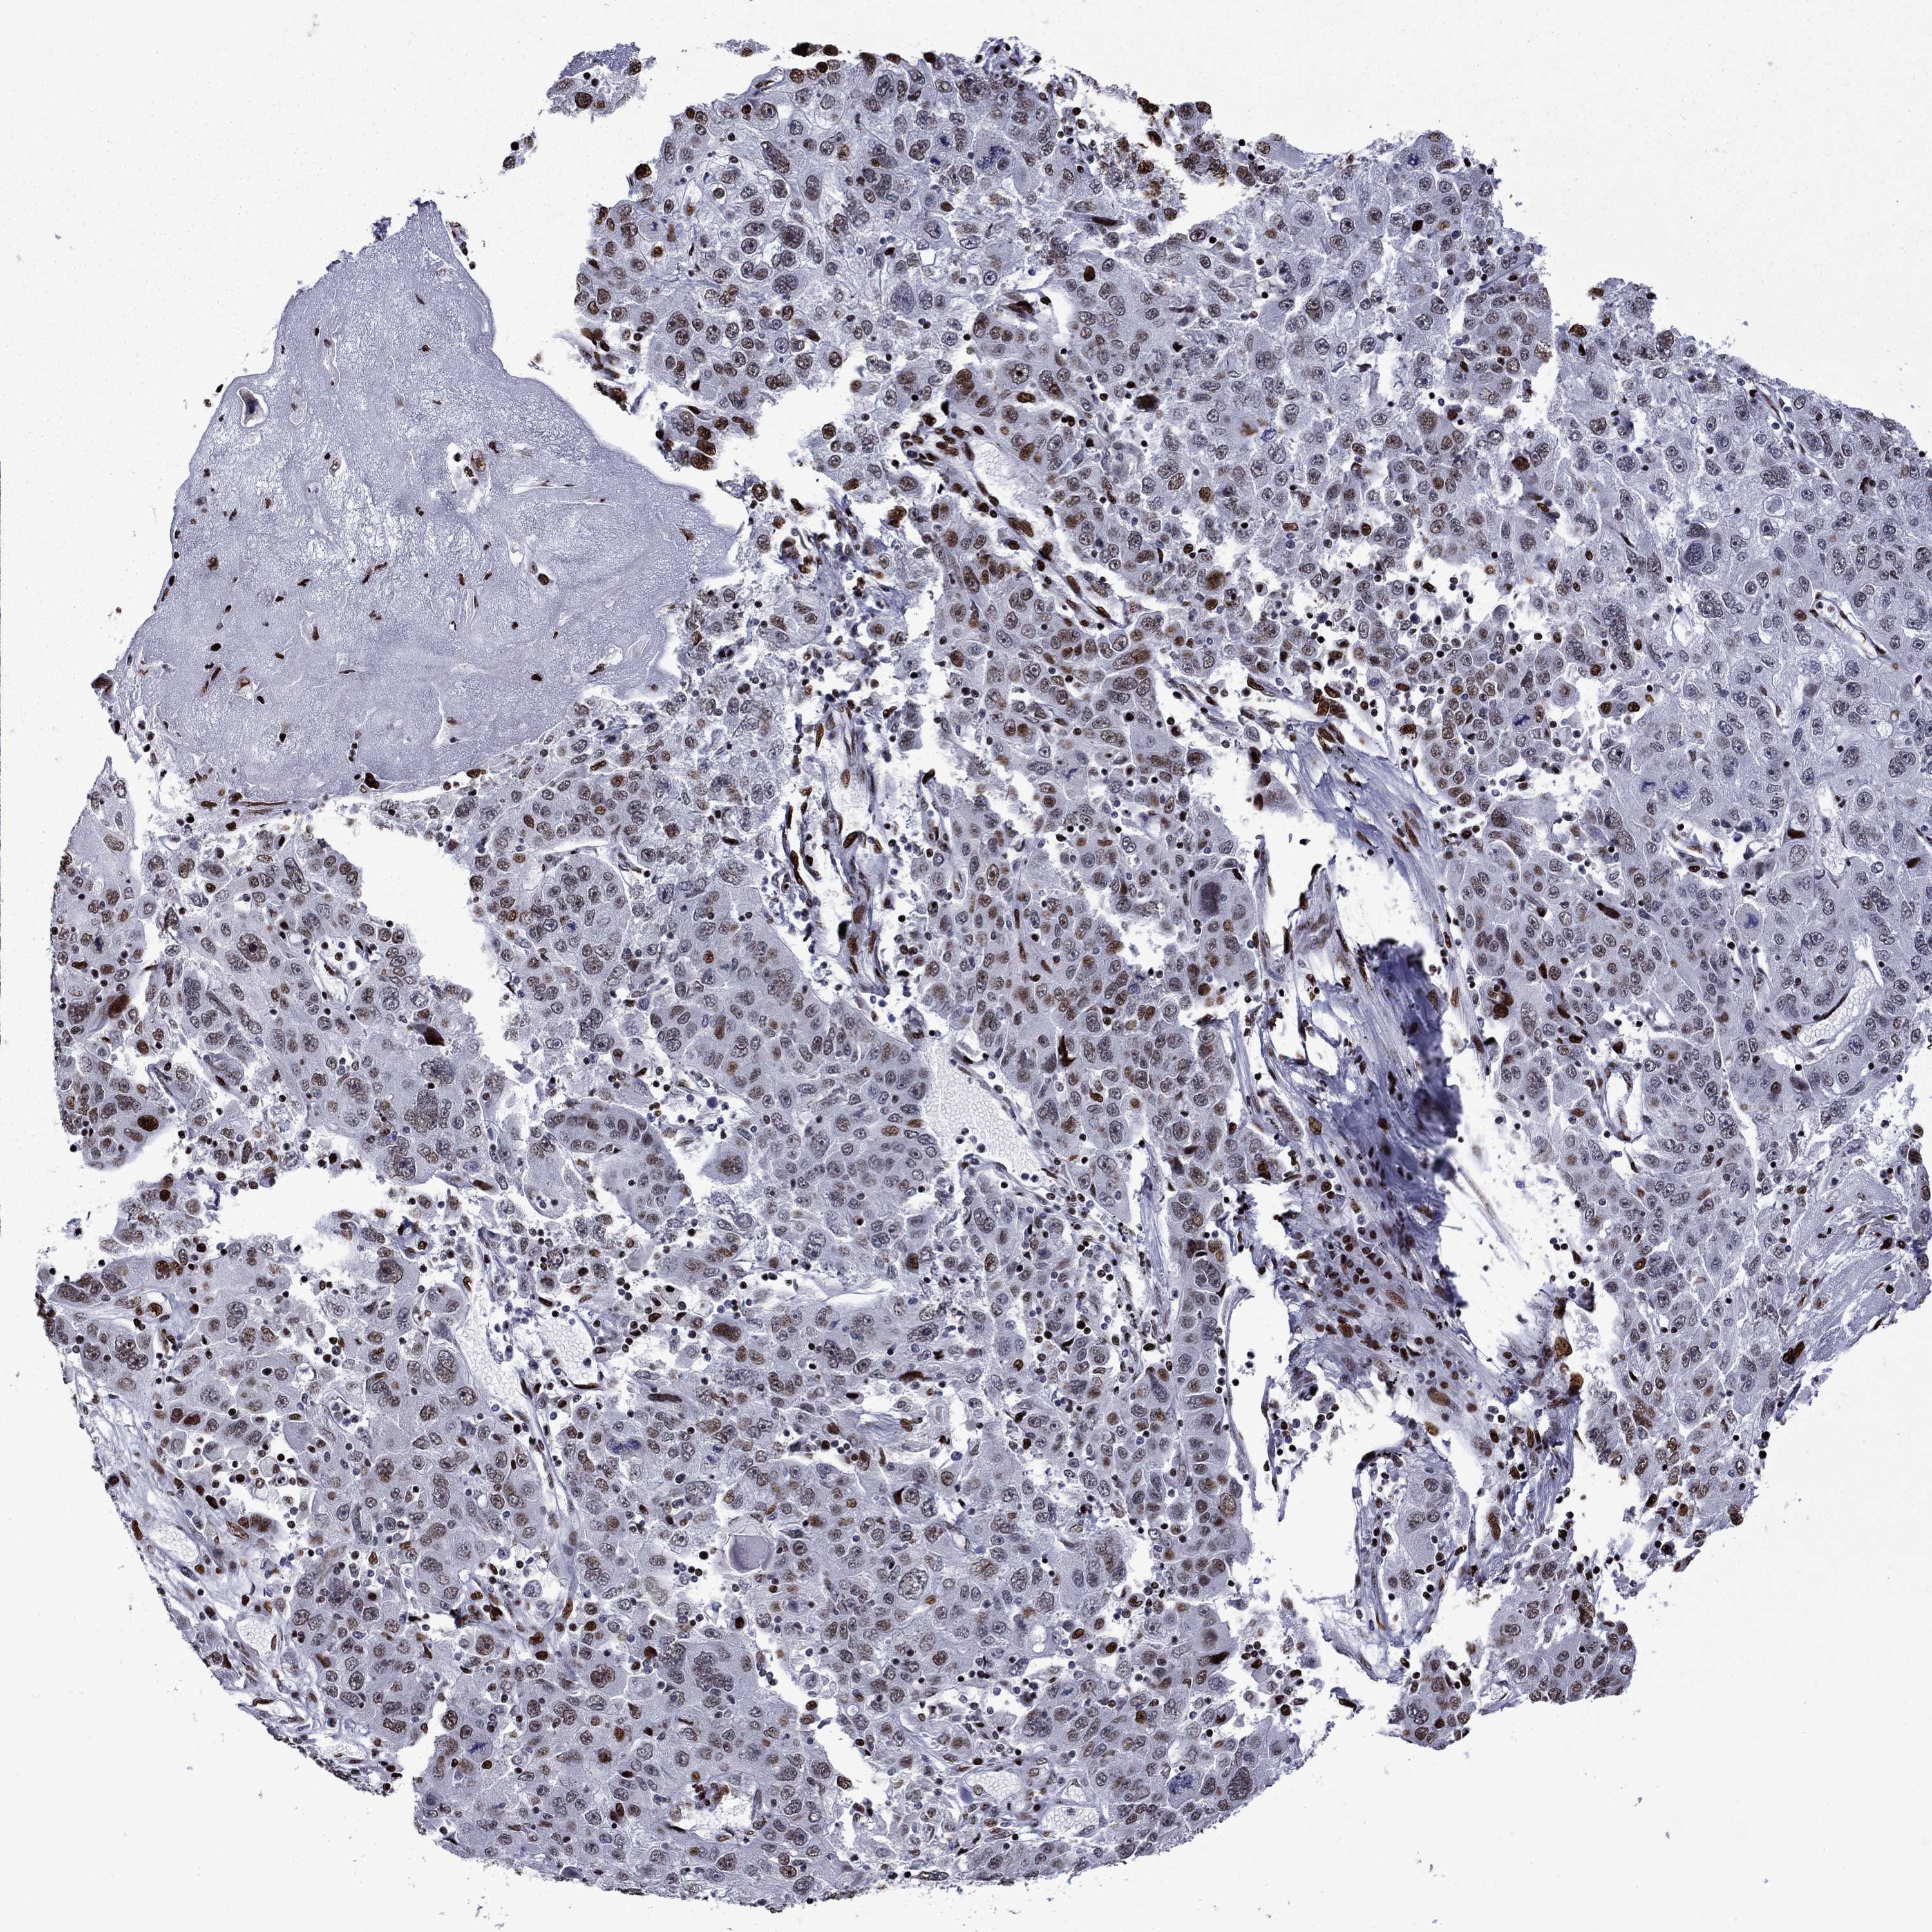

STOMACH CANCER - Protein expressioni

A mouse-over function shows sample information and annotation data. Click on an image to view it in a full screen mode. Samples can be filtered based on level of antibody staining by selecting one or several of the following categories: high, medium, low and not detected. The assay and annotation is described here.

Antibody stainingi

Antibody staining in the annotated cell types in the current human tissue is reported as not detected, low, medium, or high, based on conventional immunohistochemistry profiling in selected tissues. This score is based on the combination of the staining intensity and fraction of stained cells.

Each image is clickable and will lead to virtual microscopy that enables deeper exploration of all samples and also displays staining intensity scores, fraction scores and subcellular localization as well as patient and tissue information for each sample.

Antibody HPA028516

Antibody HPA073571

Staining

High

Medium

Low

Not detected

Intensity

Strong

Moderate

Weak

Negative

Quantity

>75%

75%-25%

<25%

None

Location

Nuclear

Cytoplasmic/membranous

Cytoplasmic/membranous,nuclear

Adenocarcinoma, NOS

Adenocarcinoma, High grade